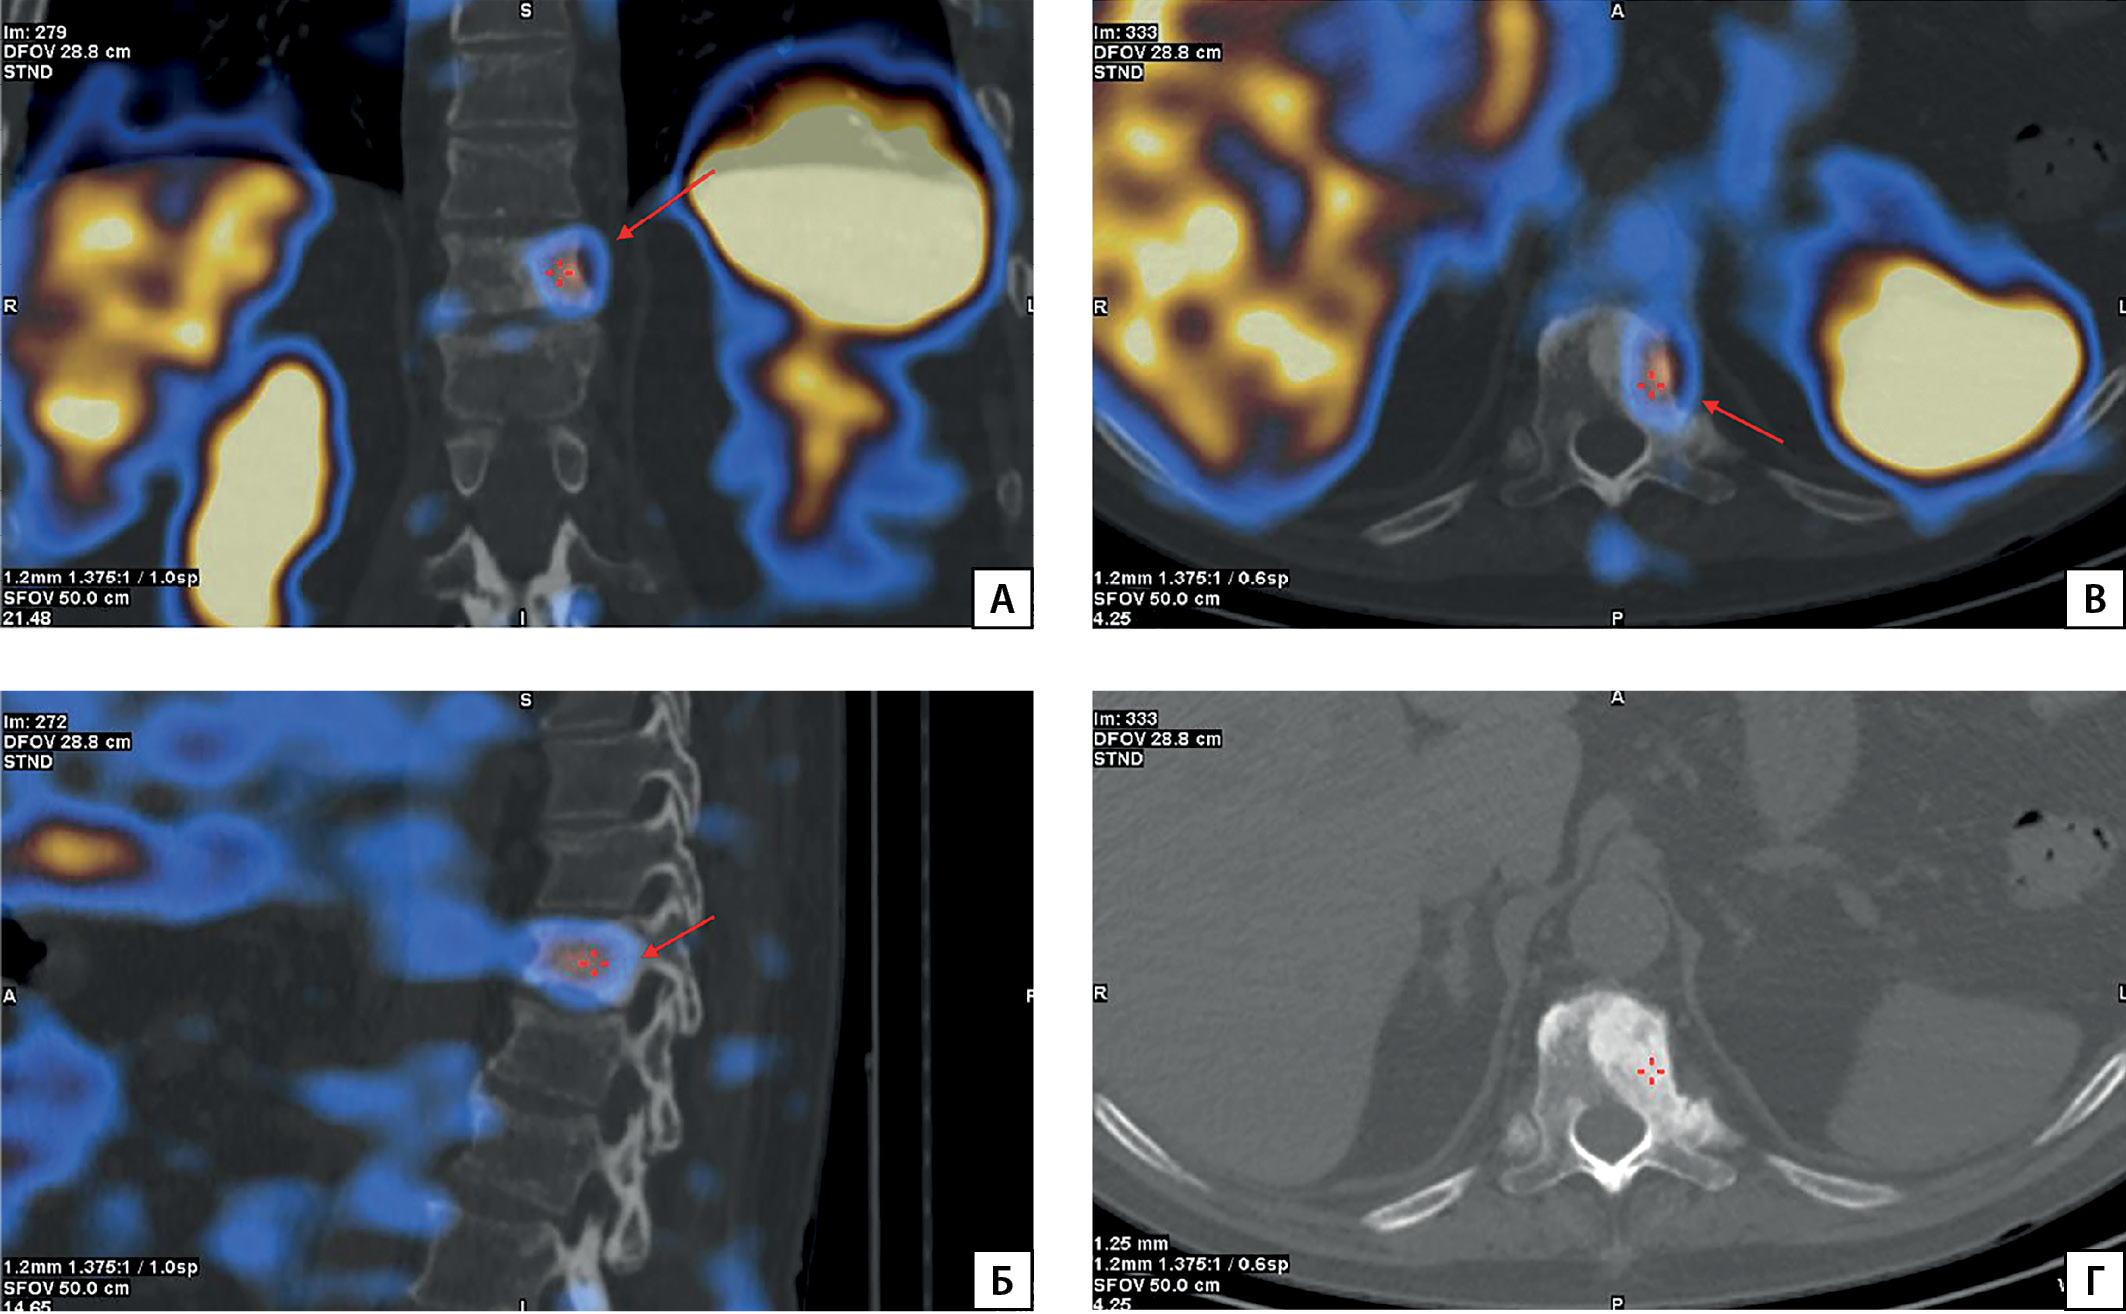

Рисунок 1. МСКТ позвоночника пациента П.

Описание: А) остеосклеротические очаги в теле Th1 и Th11 позвонков (стрелки); Б) в боковом и заднем отрезках 3-го ребра справа бластоматозная трансформация, множественные компрессионные переломы тел позвонков.

При осмотре в отделении: рост 172 см (снижение в росте на 10 см за жизнь), масса тела 85 кг, индекс массы тела 28,7 кг/м2. В ходе расширенного лабораторного обследования в стационаре сохранялись гипофосфатемия в сочетании со сниженным индексом тубулярной реабсорбции фосфатов, повышение уровня ЩФ (табл. 1). По результатам МСКТ — патологические переломы 4–10-го ребер справа и 5–9-го ребер слева в стадии консолидации, множественные застарелые компрессионные переломы тел Th2–8, Th10, Th12, L1–3, L5, смешанная перестройка правых лонной и седалищной кости с формированием патологического перелома и остеобластическая перестройка левой седалищной кости, более соответствующие вторичным изменениям (mts), однако нельзя полностью исключить изменения, являющиеся следствием опухоль-индуцированной остеомаляции, изменения 3, 6-го ребер справа более соответствуют фиброзной дисплазии или опухоль-индуцированной остеомаляции (рис. 1, 2). На основании данных анамнеза, лабораторных и инструментальных исследований установлен диагноз «фосфопеническая форма остеомаляции опухолевого генеза», инициирована терапия препаратами фосфора и увеличена доза альфакальцидола до 4 мкг. На фоне проводимой терапии отмечалось повышение уровня фосфора с 0,38 до 0,48 ммоль/л, снижение активности ЩФ, пациент субъективно отметил уменьшение выраженности болей в костях.